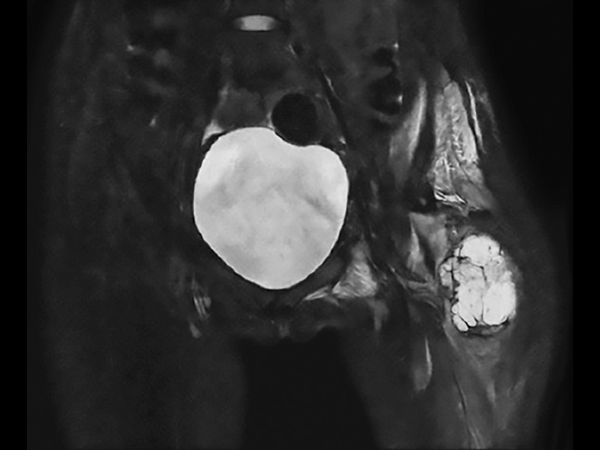

Preoperative MRI in this young girl demonstrates the large tumor with a necrotic component and areas of fluid. The tumor extends down into proximal part of femur. Edema is seen along the femoral shaft down to the knee and in the gluteal muscle. T2W mDIXON TSE in-phase and water images show the superb fat suppression of mDIXON TSE. The two-station MobiView also demonstrates the high quality mDIXON TSE fat suppression over large region and both images with and without fast suppression are obtained in about half the time needed for conventional scans.

Coronal T2w TSE mDIXON (in-phase)

Coronal T2w TSE mDIXON (water only)